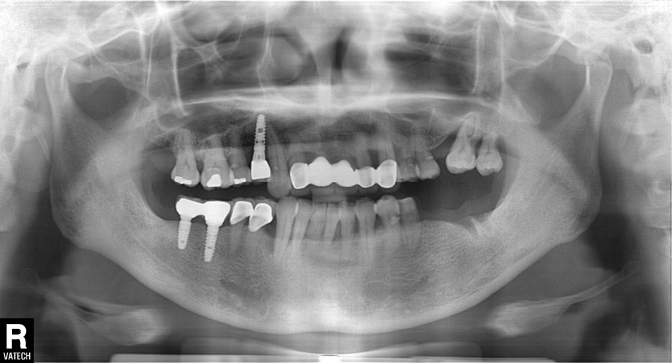

SRT

| implant model | SRT |

|---|---|

| surgery date | 2017.01.26 |

| gender | Male |

| age | 50 |